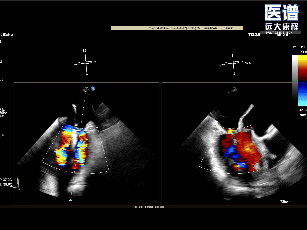

TEE

TEE-2D血流